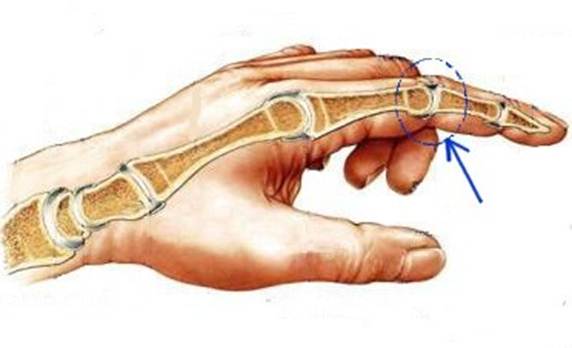

S: Стрелка указывает на art. Interphalangea manus

S: Стрелка указывает на art. Interphalangea manus

S: Стрелка указывает на art. Interphalangea manus